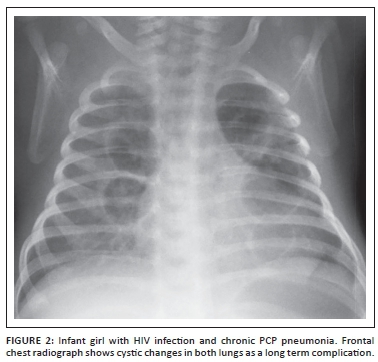

In infants with PCP and/or CMV, the radiograph usually demonstrates varying degrees of ground glass opacification that may be symmetrical or asymmetrical (Figure 1). Short term complication such as air-leaks or long term complication such as cystic lung change (e.g., pneumatocele formation) (Figure 2) may also subsequently develop.